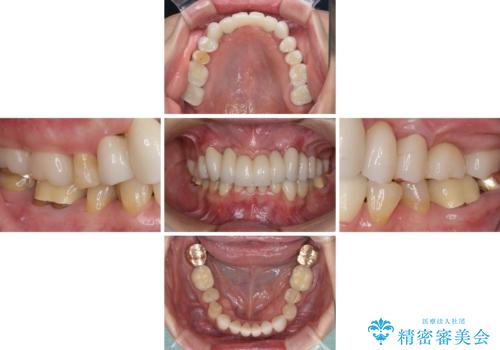

歯周外科処置を行ったことで歯周ポケットはなくなり、毎回のブラッシングの度に嫌な思いをしていた出血は認められなくなりました。

上下前歯の見え方を気にされており、歯だけをみると大変長くなりましたが、笑ったときの口元は自然な外見となり、患者様には大変満足していただきました。